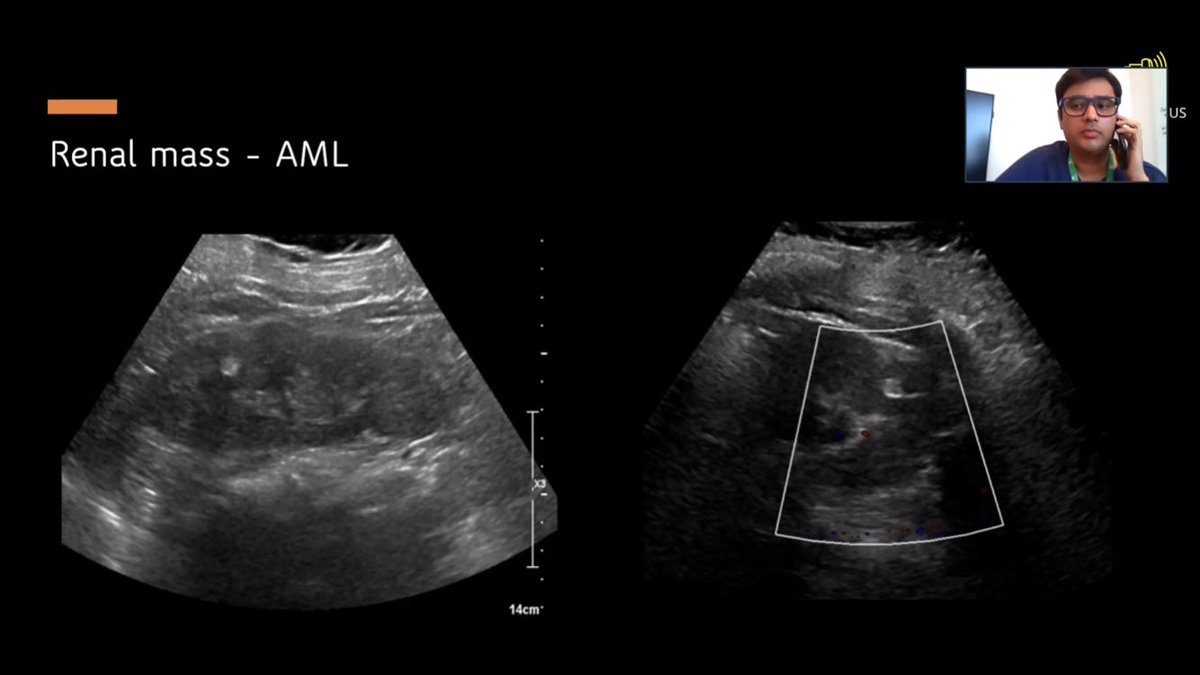

See how masses look different than cysts - hyperechoic or isoechoic lesions rather than hypoechoic #NephroPocus

Shares some pears of wisdom for mass investigation